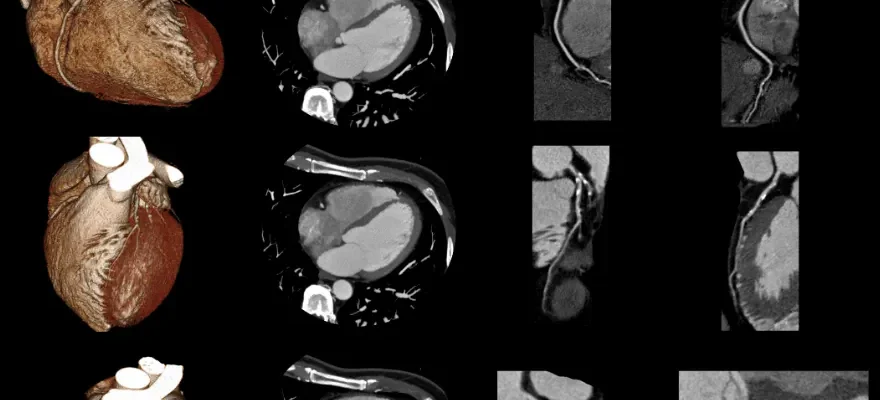

Kardiyak Koroner BT (Kardiyak Koroner Tomografi), kalbin ve özellikle koroner arterlerin detaylı görüntülerini elde etmek için kullanılan ileri bir görüntüleme yöntemidir. Bu tarama, kalp damarlarının yapısını, kan akışını ve herhangi bir daralma veya tıkanıklığı göstermek amacıyla kullanılır. Kardiyak Koroner BT, kalp hastalıklarının teşhisinde ve risk değerlendirmesinde önemli bir araçtır ve özellikle koroner arter hastalığının erken teşhisinde etkilidir.

Bu tarama yöntemi, geleneksel anjiyografiye göre daha az invazivdir ve hastalar için daha az risk taşır. Yüksek çözünürlüklü görüntüler sağlayarak, koroner arterlerdeki daralmaları, plak oluşumlarını ve kalp kasının durumunu değerlendirmekte büyük öneme sahiptir. Kardiyak Koroner BT, ayrıca kalp hastalıklarının önlenmesi ve yönetiminde de kullanılır, çünkü bu tarama ile hastalığın erken evrelerinde müdahale edilebilir.

Kardiyak Koroner BT taraması yapılırken, hasta genellikle sırtüstü yatar ve hareketsiz kalmalıdır. Tarama sırasında, BT cihazı kalp ve koroner arterlerin kesitsel görüntülerini elde eder. Bu işlem sırasında, hastanın kalp atım hızı kontrol altında tutulur ve bazen kalp atım hızını yavaşlatmak için ilaç verilir. Bu, daha net ve kesin görüntüler elde etmek için gereklidir, çünkü kalbin hareketi görüntü kalitesini etkileyebilir.

Çoğu durumda, taramadan önce kontrast madde damar yoluyla verilir. Bu, koroner arterlerin ve kalbin diğer yapılarının daha net görüntülenmesini sağlar. Tarama süreci genellikle hızlıdır ve birkaç dakika içinde tamamlanır. Tarama tamamlandıktan sonra, hastanın kalp atım hızı ve genel durumu gözlemlenir ve herhangi bir yan etki olup olmadığı değerlendirilir. Elde edilen görüntüler, daha sonra bir radyoloji uzmanı tarafından değerlendirilir ve hastanın durumuna göre tedavi önerilerinde bulunulur. Kardiyak Koroner BT, kalp hastalıklarının tanısında ve tedavisinde önemli bir rol oynar ve hastalığın erken evrelerinde müdahale edilmesine olanak tanır.

Kardiyak Koroner BT’de, özellikle koroner arterlerdeki daralmalar, plak oluşumları ve tıkanıklıklar gibi kalp hastalıkları belirgin şekilde görülür. Bu tarama yöntemi, kalp damarlarında aterosklerozun (damar sertleşmesinin) erken belirtilerini ve derecesini tespit etmek için de kullanılır. Ayrıca, Kardiyak Koroner BT, koroner arterlerin anatomik yapısını, anomalilerini ve doğumsal kalp hastalıklarını ortaya çıkarabilir. Kalp krizi geçmişi olan hastalarda, hasar görmüş kalp dokusunun ve yeniden kanlanmanın değerlendirilmesinde de bu tarama yöntemi etkilidir.

Kardiyak Koroner BT, kalp kası hastalıkları, kalp kapakçıkları ve kalbin diğer yapıları hakkında da bilgi sağlayabilir. Tarama sonuçları, kalp hastalıklarının teşhisinde, tedavi planlamasında ve hastanın takip edilmesinde önemli bir rol oynar. Bu tarama, kalp hastalıklarının erken evrelerinde müdahale edilmesini sağlar ve ciddi komplikasyonların önlenmesine yardımcı olur.